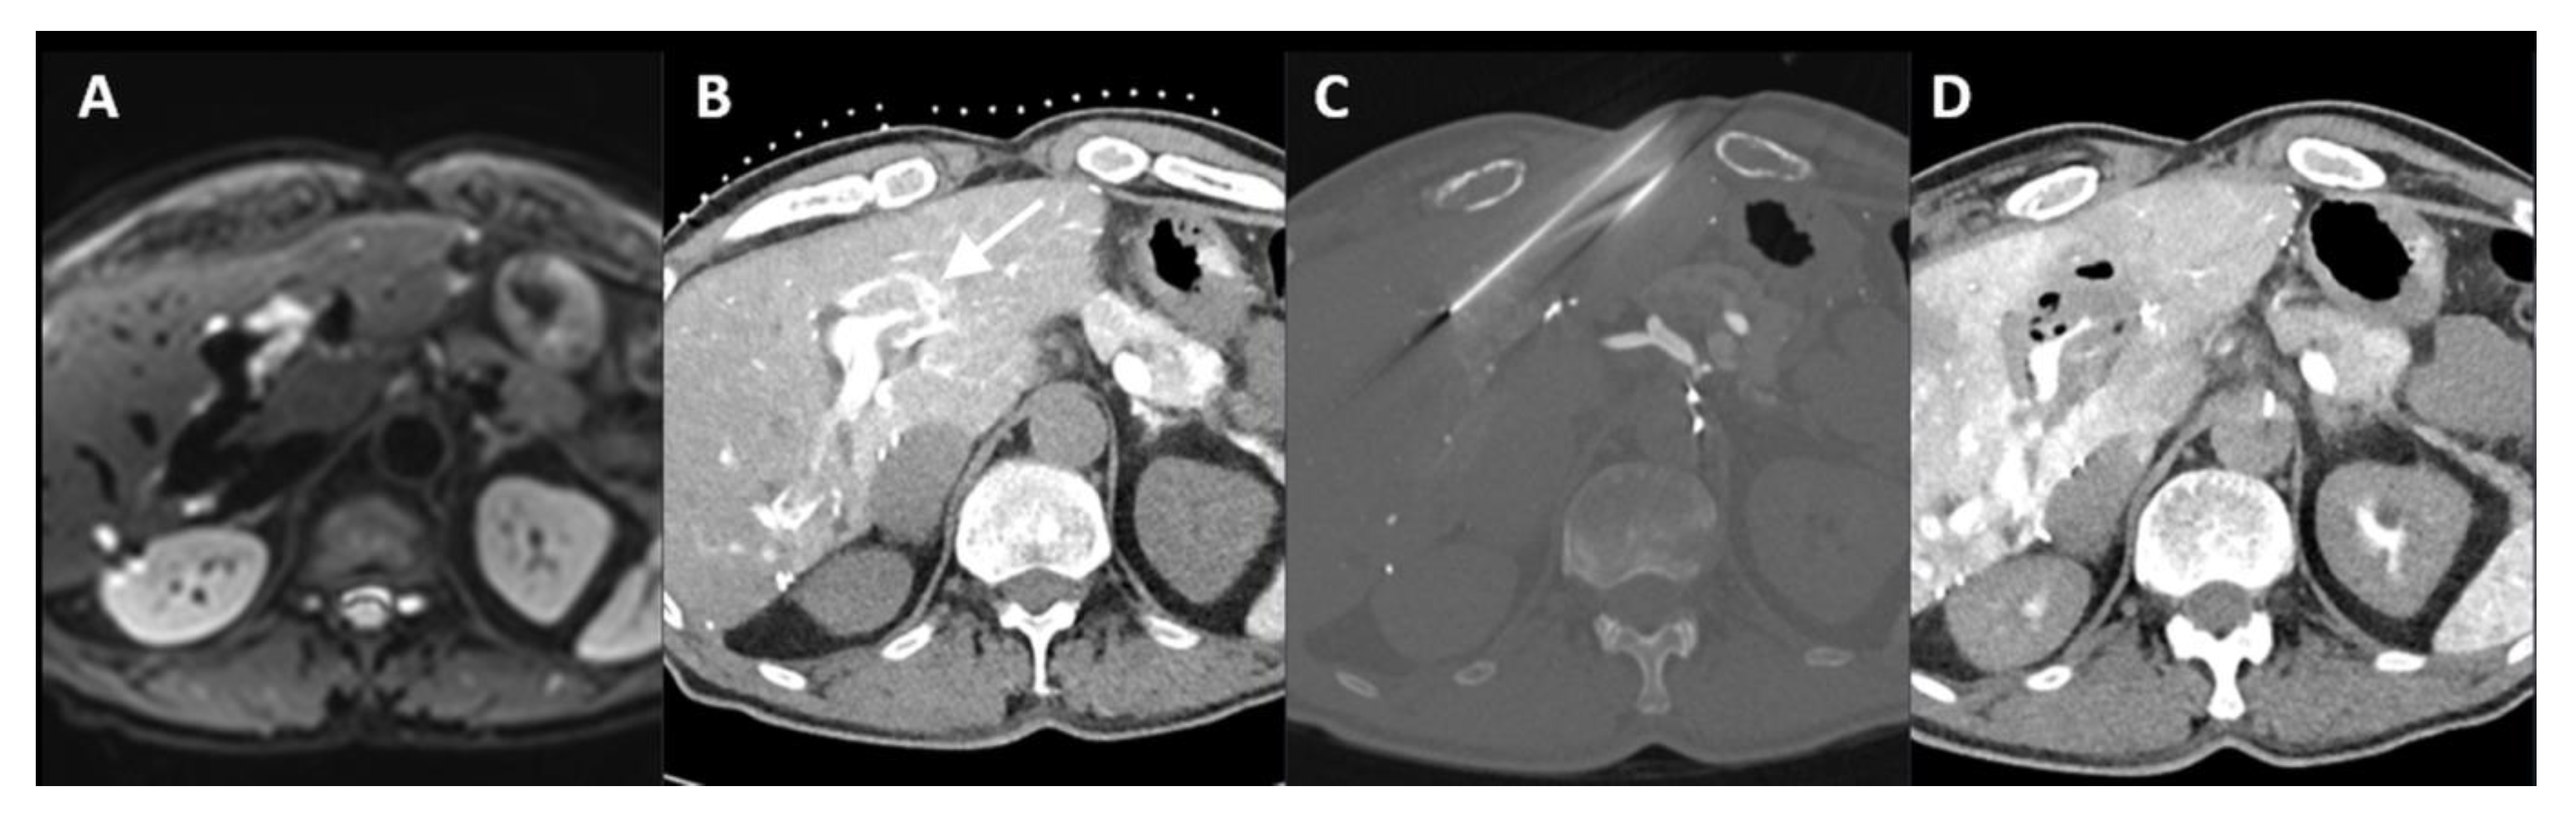

The Added Value of Transcatheter CT Hepatic Angiography (CTHA) Image Guidance in Percutaneous Thermal Liver Ablation: An Experts’ Opinion Pictorial Essay

2. Cases